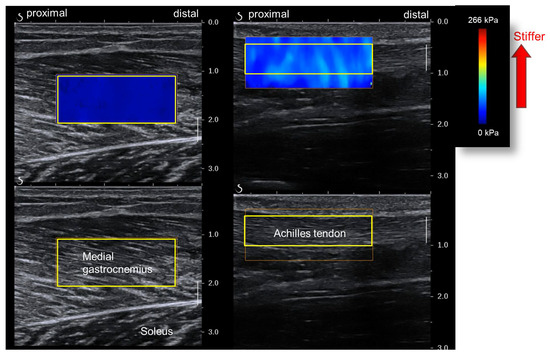

2.5. Measurement of Muscle and Tendon Stiffness

| Medial gastrocnemius shear modulus (kPa) | ||||

| 0° (neutral position) | 10.3 ± 3.3 | 8.7 ± 1.5 | 10.6 ± 3.0 | 9.7 ± 3.0 |

| DF 10° | 16.7 ± 4.4 | 15.8 ± 2.9 | 17.4 ± 6.7 | 15.9 ± 4.8 |

| DF 20° | 32.3 ± 8.5 | 29.4 ± 7.1 | 33.7 ± 8.8 | 30.6 ± 8.9 |

| Achilles tendon shear modulus (kPa) | ||||

| PF 20° | 78.4 ± 24.1 | 78.8 ± 27.4 | 81.5 ± 17.7 | 86.6 ± 24.5 |